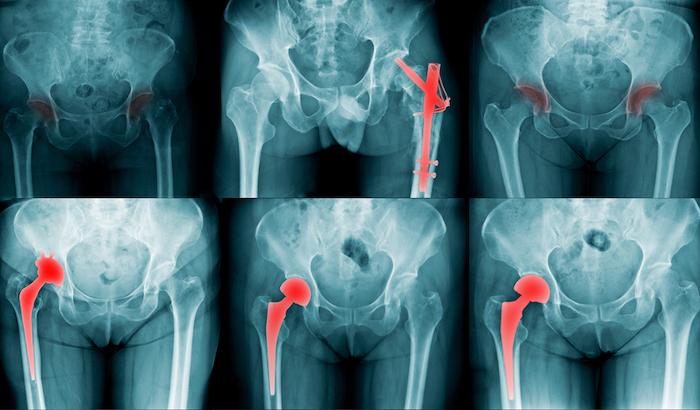

Les fractures de fragilité constituent un problème majeur qui affecte plus de 9 millions de personnes dans le monde chaque année. L’ostéoporose entraîne une fragilité osseuse et un risque accru de fractures, en particulier de la hanche, de la colonne vertébrale et du poignet. Environ le quart des personnes de plus de 50 ans qui ont une fracture de hanche meurent dans l'année suivant la fracture.